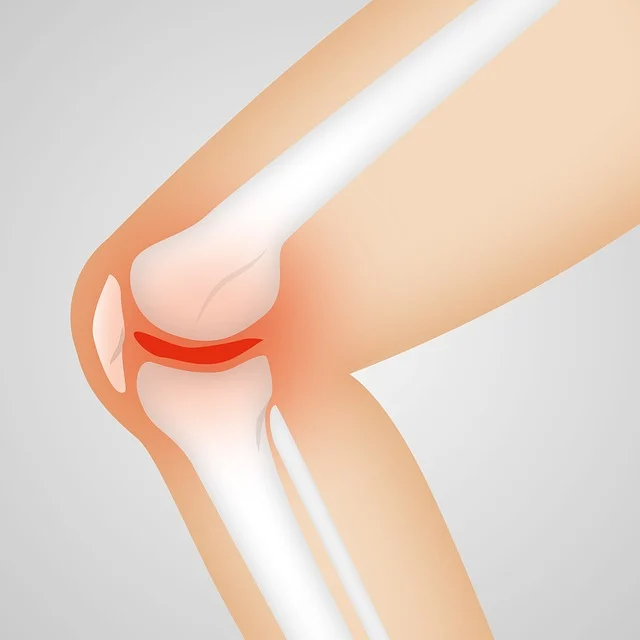

콘드로이친은 연골의 중요한 구성 성분 중 하나로, 연골 세포가 수분을 유지하고 충격을 흡수하는 역할을 합니다. 이 성분은 관절에 충분한 수분을 공급해 연골이 마르고 손상되는 것을 예방하며, 관절을 원활하게 움직일 수 있도록 돕습니다. 주로 글루코사민과 함께 섭취되는 경우가 많습니다.

✔️ 연골 보호 및 관절 건강 유지에 핵심적인 역할을 하는 성분입니다.

콘드로이친은 연골의 구성 성분을 보충하고, 손상된 연골의 재생을 촉진하는 역할을 합니다. 특히, 연골에 충분한 수분을 공급하여 마르거나 갈라지는 것을 방지하고, 관절이 부드럽고 유연하게 움직일 수 있게 돕습니다.